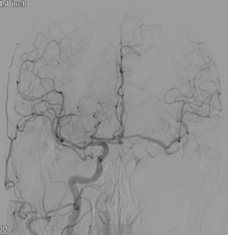

【画像4】DSA(右総頸動脈造影):右内頸動脈の血流が前交通動脈を介し、左大脳半球へ遅れて造影される血流が確認できます。

DSA(脳血管撮影):右側からの前交通動脈を介した左側への血流は減少し、左浅側頭動脈(STA)から脳表血管(MCA)に良好な血流が入っているのが確認できます。